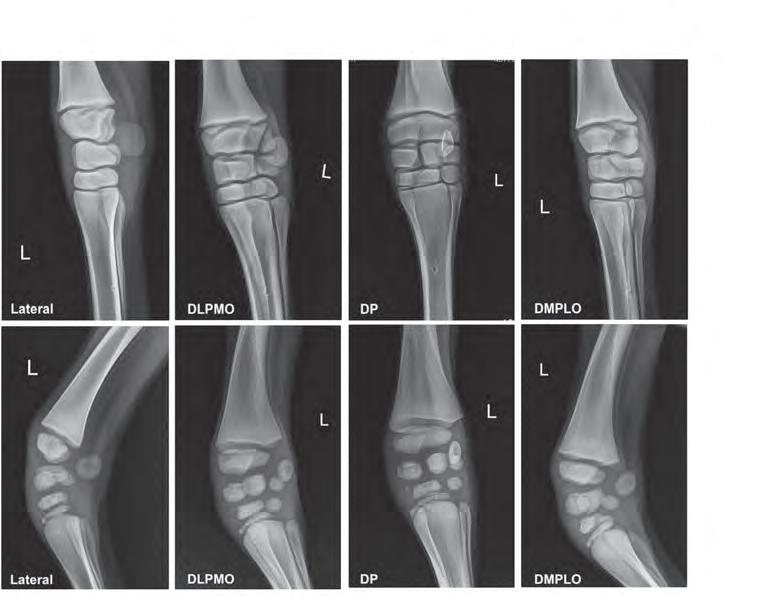

Designed in 1988, this system uses film cassettes and one radiographic view of the knee (carpus) and hock (tarsus) for assessing a foal’s bony development. It’s especially used in cases where a foal is premature (gestation under 320 days), has a poor functioning thyroid (hypothyroid) or has a long gestation of over a year with signs of prematurity (dysmaturity).

Card and her colleagues are conducting a study that uses a four-view series of digital radiographs to re-evaluate the scoring system. Team members include Dr. Jasmine Gu, Dr. Maria Lopez Rodriguez and Dr. Alannah Friedlund of the WCVM, veterinary students Brooke Tonkin and Garrett Beatch, and WCVM Veterinary Medical Centre staff. Dr. Gillian Haanen, a Calgary-based veterinarian, is also part of the team.

Digital radiography produces higher resolution images that can undergo post-processing. Manipulating the contrast or size of these X-rays allows researchers to perform a more comprehensive assessment.

These X-ray images compare the equine carpus (knee) of a healthy foal (top) to a foal affected by CHDS (bottom). Both foals were less than one week old. Brooke Tonkin